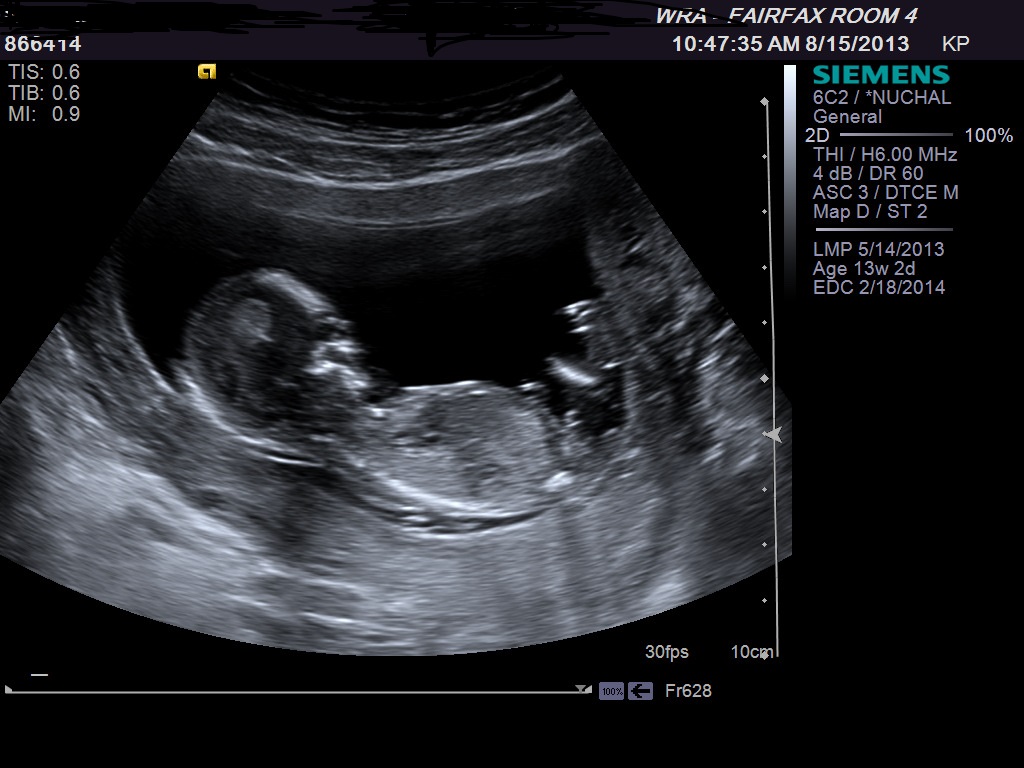

How far along are you? Thinking maybe girl...